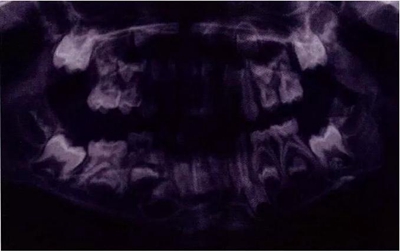

圖11是一張曲面體層片,上面顯示了一名九歲男孩同時患有55,75,和85的下沉。其55和85 為中度下沉,75為輕度下沉。這幾顆牙都沒有齲齒,都伴有恒牙胚的存在,并且沒有鄰牙傾斜和間隙喪失的臨床表現(xiàn)。給予這個孩子的方案是醫(yī)囑三個月常規(guī)復診以觀察監(jiān)測這些牙的下沉情況。結(jié)果這些牙均未加重至超過中度下沉,并且全部自然脫落,恒牙正常萌出。

文獻直達|乳磨牙下沉的臨床管理

圖11:曲面體層片顯示一名9歲男孩乳磨牙下沉,繼承恒牙胚存在。